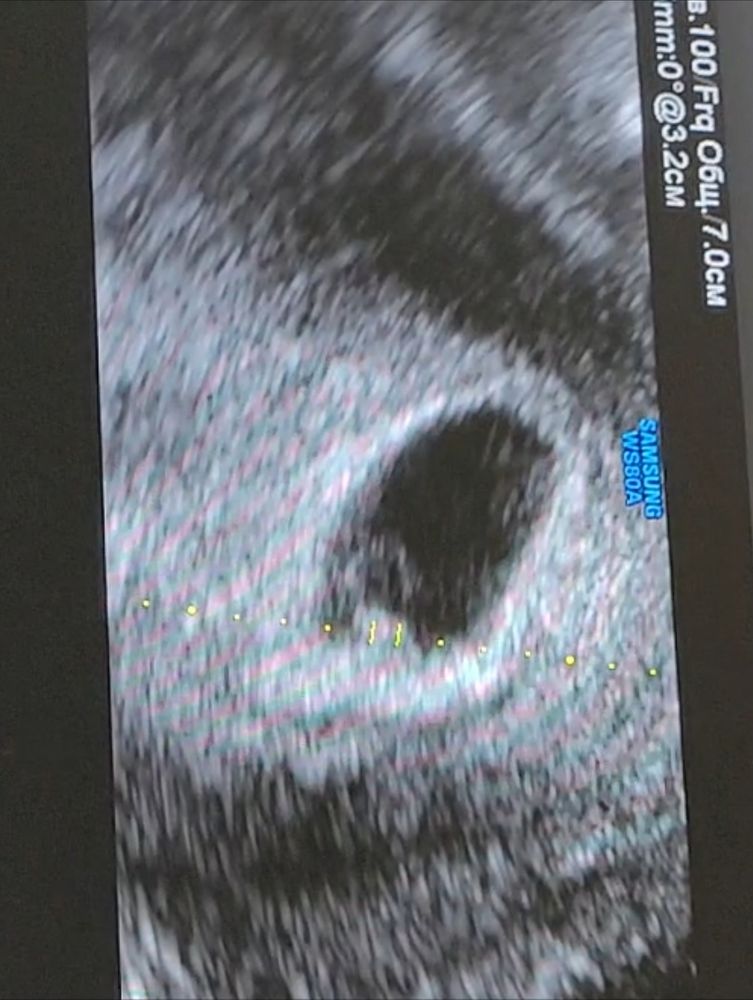

Интересно попробовать, тем более, что скоро узнаю пол точно) сделала всё, как вы сказали, только вот не могу понять, на моем фото хориона больше по правой стороне?

Это 8+4

Ваше предложение? Интересно послушать